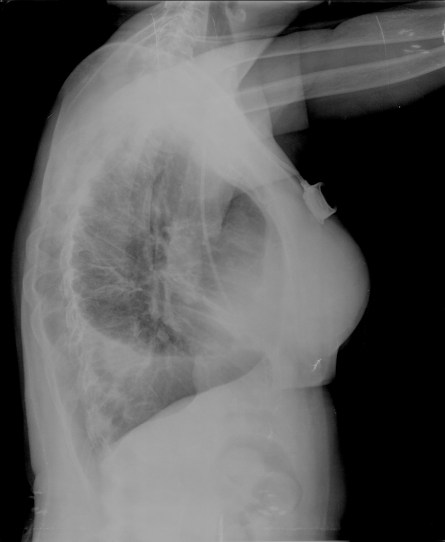

CASO: Operada de cáncer de mama izquierda en revisión.

Hallazgos:

- Prótesis mamaria izquierda (obsevar el aumento de densidad homogéneo y de bordes bien definidos en la placa PA y lateral)

- Parénquimas pulmonares y silueta cardiomediastínica sin alteraciones significativas.